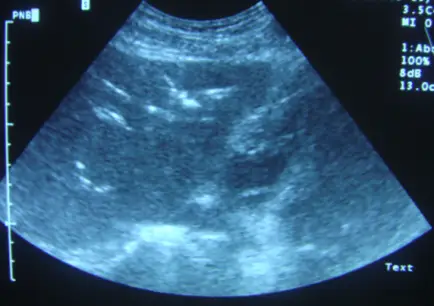

下圖為肝臟超音波掃描,最可能的診斷為:

本題聚焦於肝臟超音波影像中「肝內高回聲結構」的鑑別診斷,主要要區分氣體(pneumobilia)、結石(intrahepatic bile duct stones)、寄生蟲(hepatic ascariasis)或腫瘤(hepatocellular carcinoma)所呈現的超音波特徵。

從提供的肝臟超音波掃描圖可見:

- 肝門區(central portion)出現多條線狀或分支狀極強回聲(highly echogenic)結構,分佈呈樹枝狀沿肝內膽管走行。

- 這些高回聲結構未形成明顯的後方聲影(posterior acoustic shadowing),而是產生「ring-down」或“dirty” reverberation artifact。

- 回聲結構位置集中於肝臟中央,不像門靜脈氣體會在肝周圍(periphery)呈現;也未見可明顯外框成團塊狀的腫塊。

- 在影像中可觀察到回聲條帶隨機位移或探頭擠壓時輕微改變,符合氣體受重力與探頭壓力影響而改變分佈特性。

上述影像特徵與肝內膽管氣體(pneumobilia)典型所見相符:中央性、線狀分支、ring-down artifact,且無清晰聲影([thepocusatlas.com](https://www.thepocusatlas.com/new-b